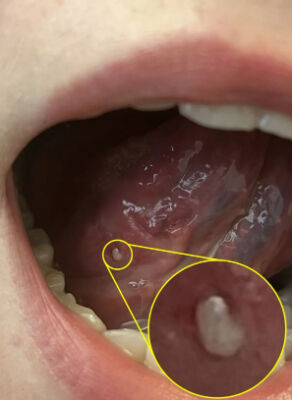

Birleşik Krallık’ta yaşayan 23 yaşındaki bir kadın, yemek yerken ve esnerken dayanılmaz bir acı hissetmesi üzerine doktora başvurdu. Doktora gitmeden önce ağzında ülser olduğunu düşünen genç kadına biyopsi yapıldı. Yapılan testlerin sonucunda kanser olduğu tespit edildi. Dildeki tümörü temizleyen doktorlar, kadının kolundan alınan bir deri parçasını bölgeye nakletti.

Mirror’un haberine göre uzun süre boyunca yemek yerken ve esnerken acı çeken Rowell, soluğu hastanede aldı. Ağustos ayında diline biyopsi yapılan genç kadına birinci evre kanser teşhisi kondu.

Dildeki tümörün alınması için harekete geçen doktorlar, kanserli bölgeyi temizleyerek kadının kolundan alınan bir deri parçasını bölgeye nakletti.